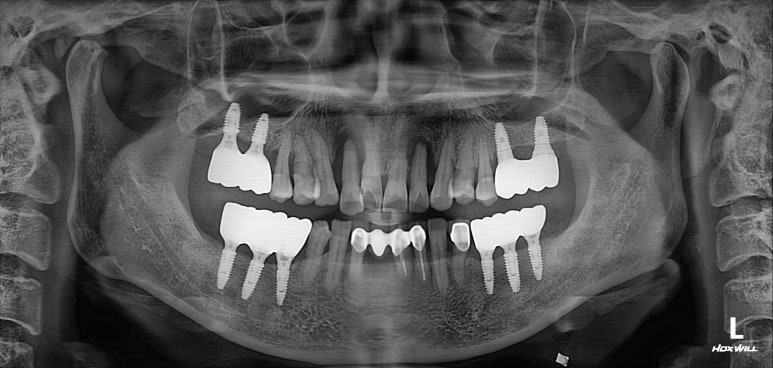

엑스레이를 보시면, 양쪽 위턱 가쪽 앞니가 거의 잇몸뼈와 분리되어 둥둥 떠있는 모습을 보실 수 있습니다.

잘 모르시겠다면, 제가 표시해드리겠습니다..!!

점선이 실제 잇몸뼈의 높이를 나타내고 있습니다.

노란 화살표로 표시한 두개의 위턱 측절치가 남아있는 뼈 없이 둥둥 떠있는 모양이에요.